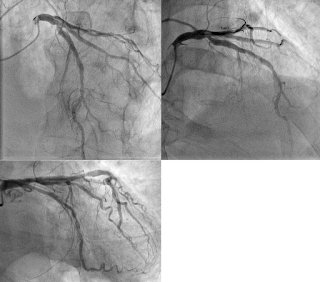

昨日、MSの術前の患者さんで、複数回PCIを受けている患者さんの術前カテーテルがあり、LAD DX 分岐部に50/75%の狭窄とLCXに75%の狭窄があり、なんと道井院長のほうから、FFRをLADにしてくれというオーダーがあり、 FFRでは低下がなく、これはバイパスがLADに必要ないので、MSとバイパスをLCXのためにやる必要はないので、LCXは、MSの術後に治療するようにという、オーダーでした。

症例は、FFRした症例です。